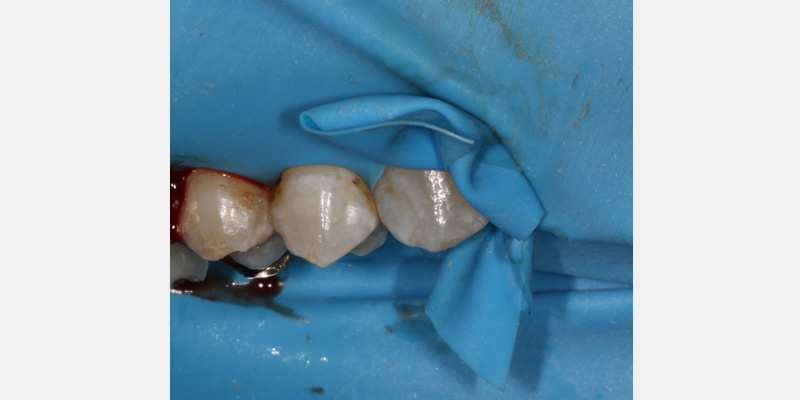

Rubber dams can be very useful for everyday restorative dentistry procedures, such as cases where deep carious lesions present a risk of pupal exposure, restorative procedures next to recent extraction sites, and anterior cases where tissue retraction is necessary.

Furthermore, when caustic solutions like hydrofluoric acid are used intraorally for ceramic repairs, rubber dam isolation prevents damage to the adjacent tissues. Rubber dam usage is still considered the standard of care for specific procedures, such as endodontic therapy.

Invariably, leakage may still occur. After the rubber dam is placed, a caulking material can seal any areas that may still have leakage. Various products are available on the market; however, unbonded composite can also be placed and light-cured to act as a caulking agent.

In some instances, light or open contacts may exist between adjacent teeth, which can present a challenge for securing the dam. Fabricating a floss ligature using a square knot can help secure the dam around the tooth. If this does not work, a thicker material (such as a Wedjet) can be used to hold the dam in place. Alternatively, a corner of the dam can be cut off and used interproximally to secure the dam.